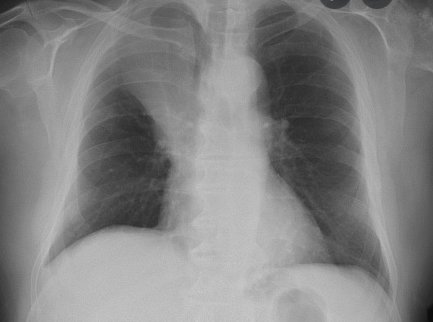

What investigations are done in a 2 week wait referral for suspected lung cancer and what will they show if it is lung cancer?

Chest X-Ray!!!!

• Focal lesion

• Pleural effusion

• Widened mediastinum due to enlarged hilar lymph nodes

• Diaphragm collapse